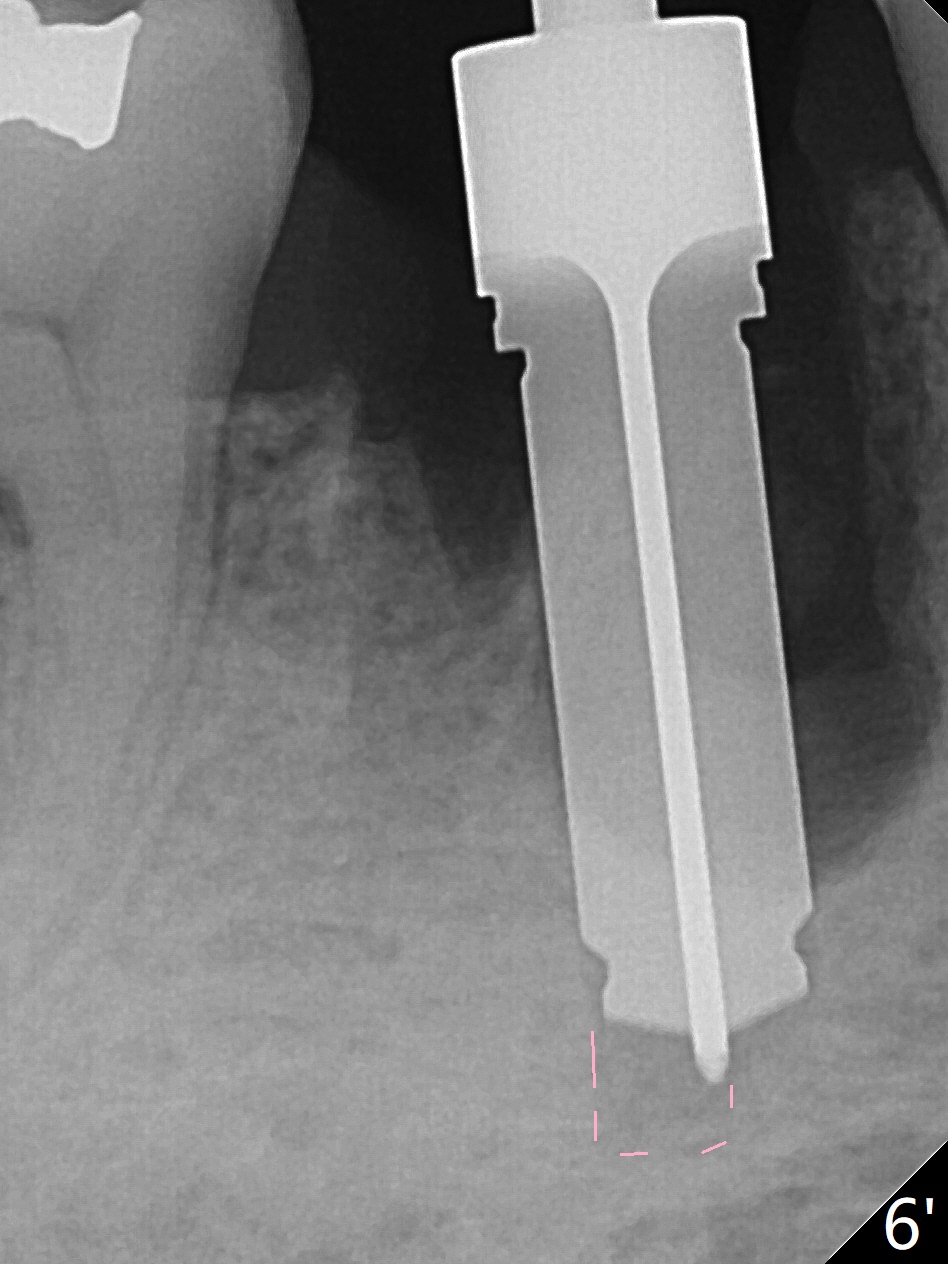

Preop oral Amoxicillin seems to be associated with reduction in the buccal and lingual (Fig.3 arrow) fistulae at #30, but there is mesiobuccal swelling (Fig.1 *) with 7 mm pocket (Fig.2). Osteotomy is initiated in the middle of the septum (Fig.3-5 S). As the osteotomy increases, it shifts mesially (Fig.6 arrow). Guided surgery is able to reduce shifting. A 5x13 mm implant is not seated completely (Fig.7) apparently due to osteotomy shifting. After removal of the bone from the osteotomy distally, the implant remains unseated with lower torque value (Fig.8). Following reuse of the 4.3 mm drill deeper by 1-2 mm, the implant is seated to a satisfactory depth (Fig.9 with increase in torque to 50 Ncm) with placement of Vera Graft (*) and a 7.5x4(3) mm abutment. After a second round of allograft placement (Fig.10 *), the implant is found to be 4 mm from the IAC. At the later stage of osteotomy, the coronal end of the septum is destroyed with loss of osteotomy depth landmark. It is apparent that the soft tissue landmark may be more reliable. The implant threads appear to be covered by the bone graft 3.5 months postop (Fig.11). The abutment is changed to 6.5x5(3) mm one before impression with minor margin prep. The bone density seems to increase 5 months postop, i.e., immediately post cementation (Fig.12) and 10 months postop (5 months post cementation (after retightening abutment), Fig.13 (*)). Periimplantitis develops mesiobuccally, consistent with bone loss 1 year 7 months post cementation (Fig.14 *); the implant seems to have been buccally placed. Bone graft is necessary with PRF or GEM21S if the vein is small and 6-month membrane with a hole around a 7.5x4(4) cemented abutment for easy wound closure. Take 5x5 CM CBCT to determine which wall has defect, buccal or lingual. Check mesial contact. If so, remove the crown, reseat the abutment (possible incomplete seating) and re-impress after bone graft.